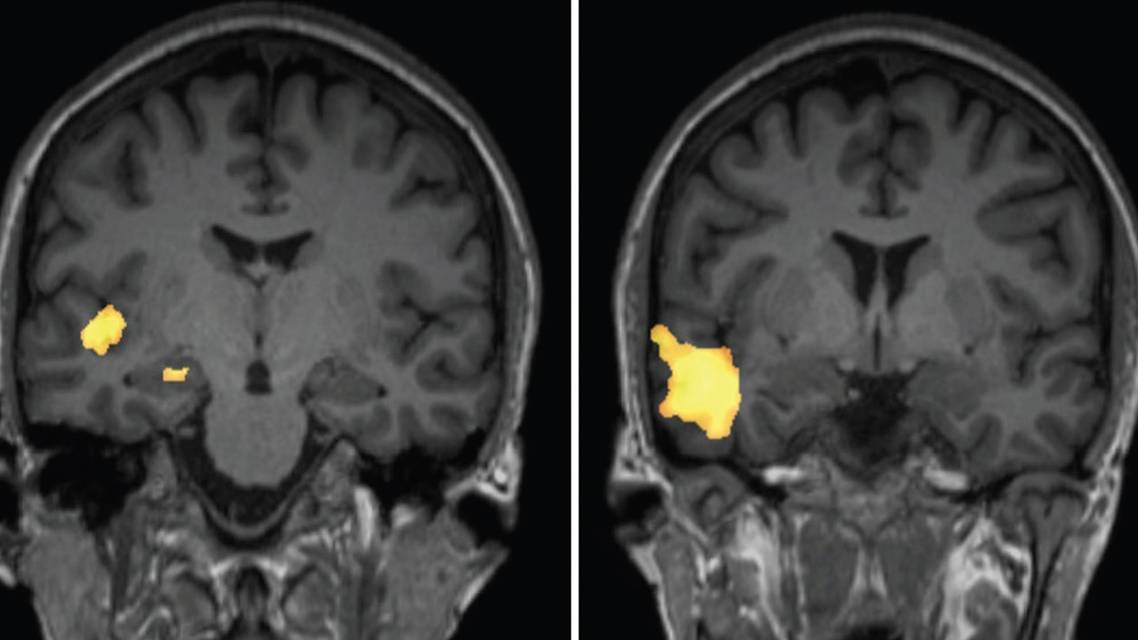

Brain MRI with and without contrast was obtained at an outside institution before admission to the EMU, which revealed no acute intracranial abnormality, mass, or epileptogenic focus. There was no evidence of medial temporal sclerosis, abnormal contrast enhancement, or structural abnormality. Continuous video EEG testing was performed, which revealed left temporal lobe epileptiform discharges and left hemisphere onset seizures. Additional localizing data were needed for presurgical planning. Interictal SPECT, obtained before the EMU admission to acquire the baseline cerebral perfusion pattern, revealed decreased perfusion in the left temporal lobe. In an effort to provoke seizure activity for acquisition of an ictal SPECT during an active seizure, antiepileptic medications were withheld, and LD listened to an emotionally powerful song that had previously triggered seizures. This triggered a seizure, and the SPECT radioisotope was delivered within 15 seconds of the seizure onset. The EEG showed activity originating from the left temporal head region (Figure 1). The ictal SPECT revealed increased perfusion in the left temporal lobe primarily involving the left anterior inferior temporal lobe, hippocampus, and insula. Subtraction of the ictal and interictal SPECT imaging confirmed a left temporal lobe focus (Figure 2).